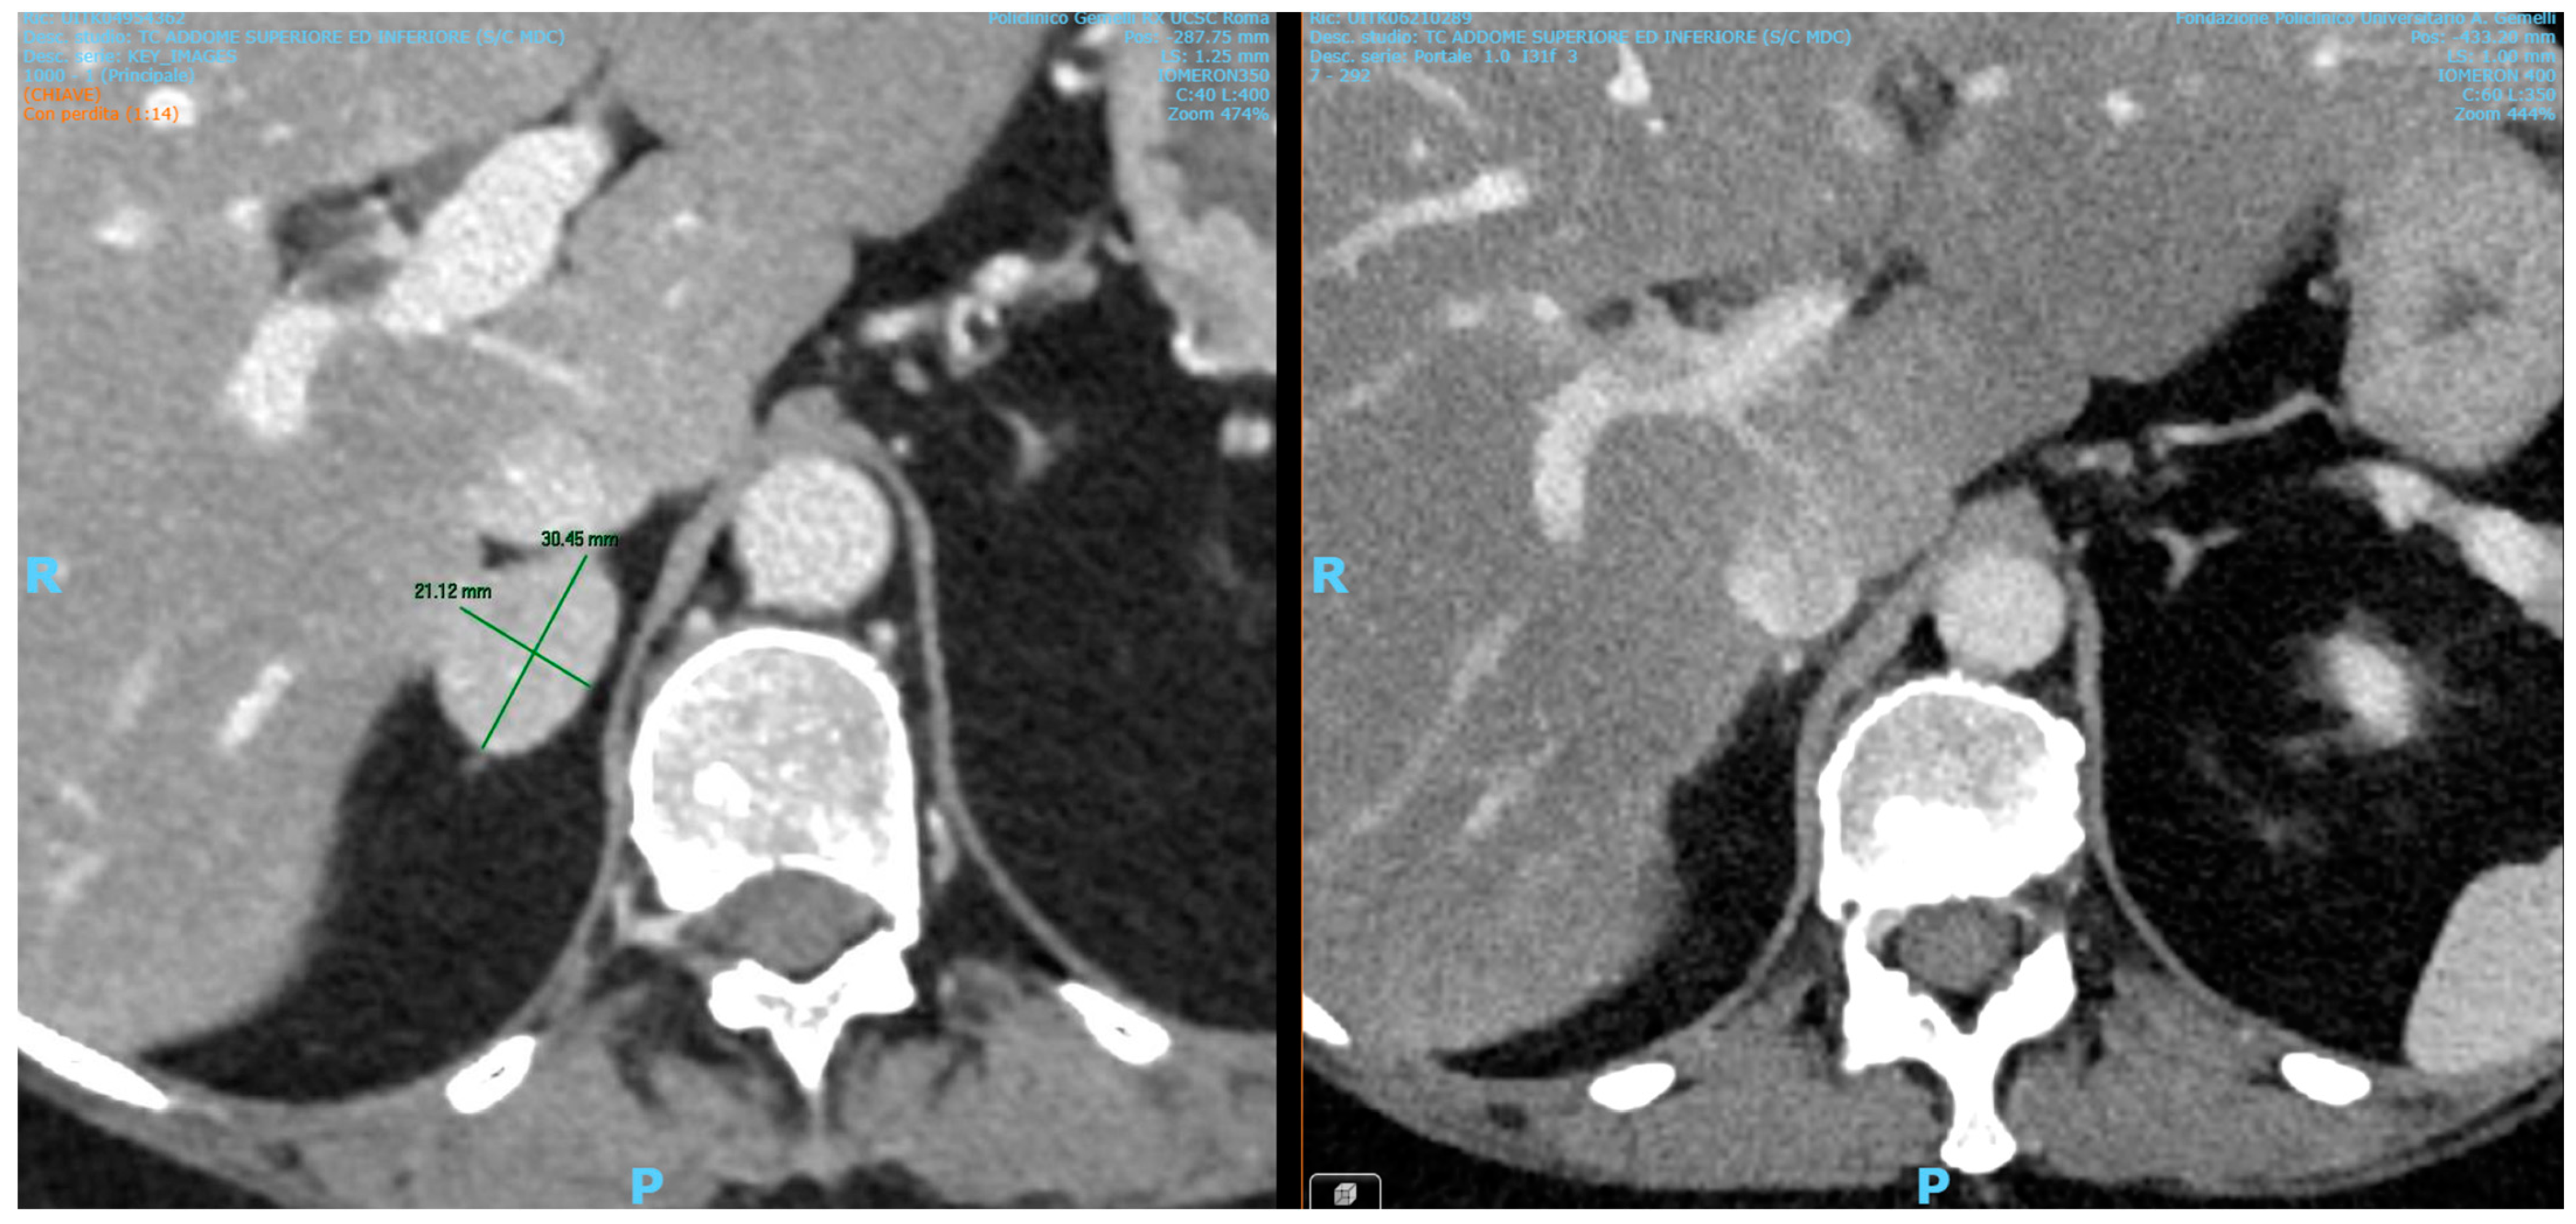

2. Case Presentation